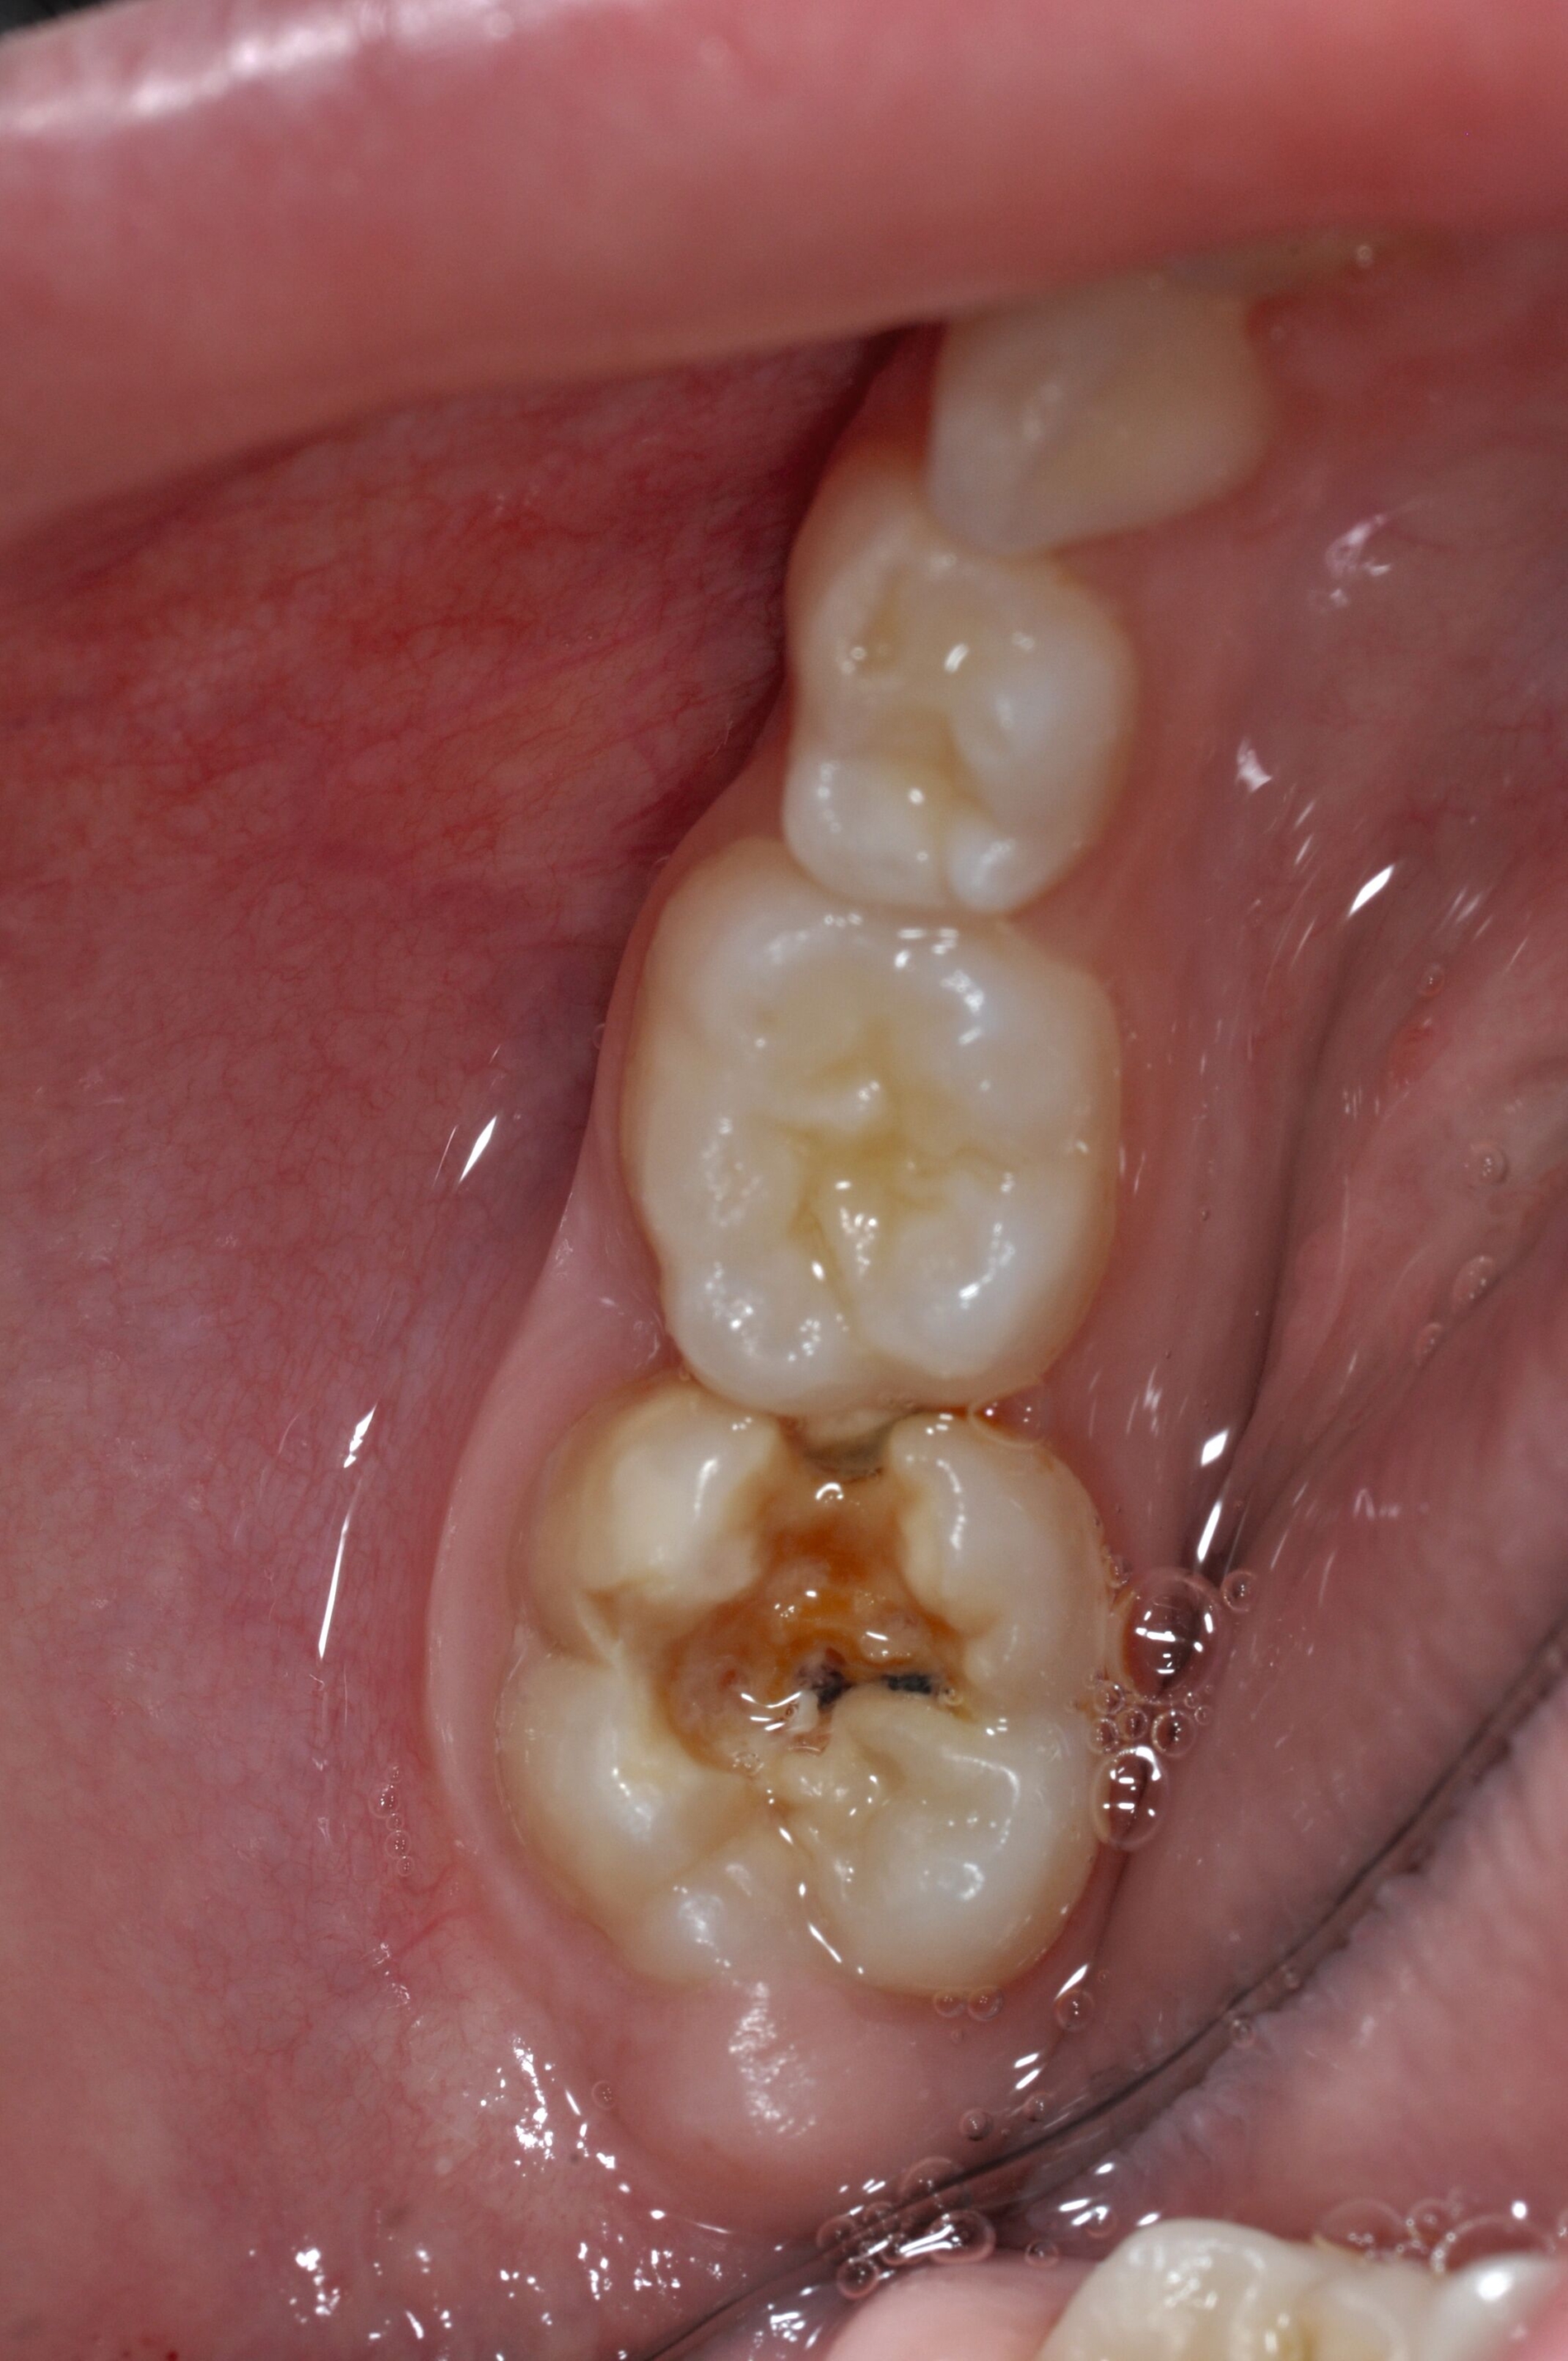

Diese Klassifikation dient als Grundlage für die Therapieempfehlungen. Deutlich wird, dass aufgrund der Symptomatik die Therapie der Zähne höchst unterschiedlich ausfällt. Dass etwa eine Opazität ohne Überempfindlichkeit (Index 1, Abbildung 1) ein anderes therapeutisches Vorgehen erfordert als ein Zahn mit nahezu komplettem Einbruch der Zahnoberfläche und mit Hypersensitivität (Index 4, Abbildung 2), ist offensichtlich.

Für die zahnärztliche Praxis gibt die Einteilung eine Orientierung darüber, welche Behandlungsmaßnahmen erforderlich sind beziehungsweise eingesetzt werden können. Je nach Schweregrad wird dabei zwischen nichtinvasiven und invasiven Maßnahmen sowie einer kurzzeitigen oder längerfristigen, restaurativen Therapie unterschieden. Bei der Überarbeitung des Konzepts wurde zudem zwischen Front- und Seitenzähnen differenziert (Abbildung 3) [Bekes et al., 2023; Steffen et al., 2017].

Die Therapie C hat das Ziel, MIH-Zähne vorübergehend zu versorgen, bis der vollständige Durchbruch der Zähne eine adhäsive Restauration ermöglicht, um die hypersensiblen Zähne zu desensibilisieren oder/und die Mitarbeit für die weitere Behandlung aufzubauen. Vor dem Hintergrund des erhöhten Kariesrisikos dieser Zähne (Abbildung 2) muss durch die Maßnahmen eine Kariesprogression vermieden werden.